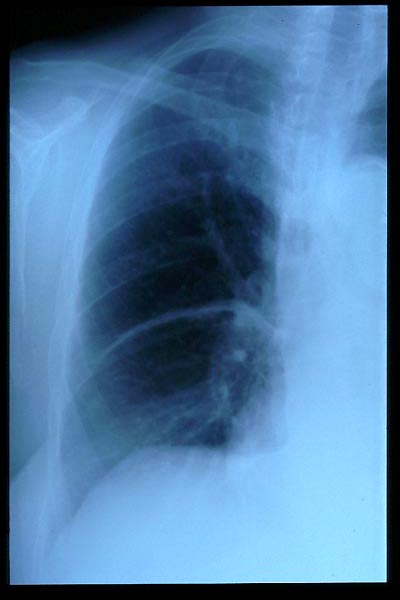

Hernia de hiato gigante.